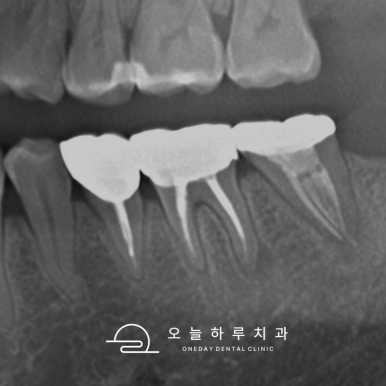

📸 케이스 4: #43 Re-Endo

- 잇몸에 여드름처럼 볼록한 염증이 올라옴

- 치근단 염증 및 헐거운 충전 확인

- 재신경치료로 염증 완치

✅ 육안으로 보이던 염증도 완전 치유